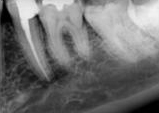

antes depois